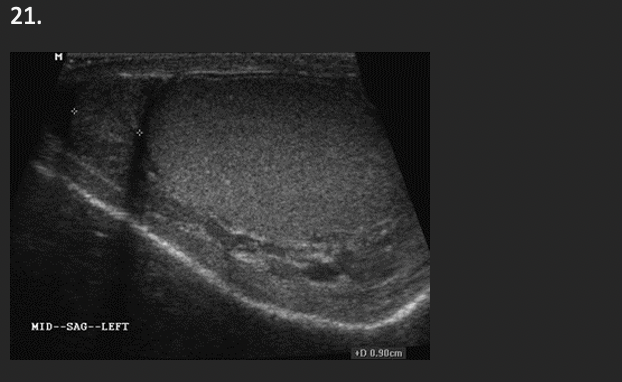

This sagittal image of the left inguinal canal an 8 month old male infant is most likely demonstrating an

C. undescended testicle